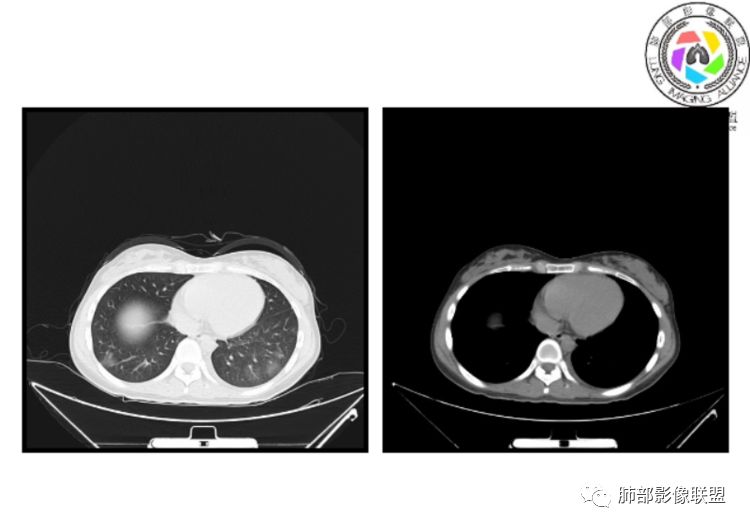

小微:右肺下叶斑片状密度增高影,抗炎治疗6天后复查,双肺下叶出现斑片状密度增高影,排除炎性病变,D2聚体特别高,考虑肺栓塞,肺梗死,建议增强扫描。王开金江津中心医院呼吸科:@岳微-辽宁PLA234医院放射科?支持,患者年轻女性,胸痛主诉,使用雌激素,高危人群,心率快,d二聚体升高,右下叶斑片加肺动脉明显增宽,抗感染无效,要考虑PTE,建议肺动脉ctpa。傅昌瑜:19岁,女性,右侧胸痛2天,发热以中度热为主,D—二聚体升高,肺动脉主干增宽,病灶位于胸膜下,抗感染后增多,近来有服用炔雌醇环丙孕酮片2周期史,诊断:肺栓塞,下一步完善肺CTPA检查。阿仙奴:青年女性,急性起病,胸痛入院,月经不调史,目前服用孕酮片。流感抗体阳性,d二聚体升高,无低氧血症。右肺下叶基底段胸膜下磨玻璃样改变,肺动脉增宽,治疗过程出现发热,复查左下叶胸膜下新发病灶。考虑:肺栓塞(服用孕酮相关)?奔跑的37°Doctor(陆喜红 ) :年轻女性,胸痛 急性病程,有服用雌激素避孕药史(是否有血液循环的改变,高凝状态),实验室D二聚体很高(也是提示血液高凝状态) ,第一次CT,右下肺胸膜下斑片状密度增高模糊影,肺动脉形态密度未见明显异常,抗炎后复查,肺动脉干及其分支,感觉增粗了一点,局部形态有点饱满,双下肺胸膜下片状影增多,锁定肺动脉栓塞应该不会错,建议CTA检查飞鹰行动:青年人,女性,右肺下叶斑片状密度增高影,抗炎治疗6天后复查无好转,,双肺下叶出现斑片磨玻璃影,主肺动脉增粗,结合患者服用的药物和D2聚体特别高,考虑肺栓塞,建议CTA。李:口服避孕药,有危险因素,肺动脉较主动脉增宽,D二聚体增高,胸膜下片状影,考虑肺栓塞;@晨义工张帅,医附属潞河医院呼吸?是否痰中带血很关键,不知有没有张帅:患者入院后第七天出现痰中带血风之子:病程中有发热,D—二聚体升高,肺动脉主干增宽,病灶分布于胸膜下,抗感染后增多,结合服药史诊断:肺栓塞,建议CTPA检查。不支持的地方是没有低氧血症,不明白为什么第二次复查ct双侧乳腺不对称,按理乳腺炎多见于哺乳期张帅:大家方向都在考虑肺栓塞:我提问两个问题:1 周围毛玻璃怎么回事?2左下肺小叶间隔增宽怎么回事?笨丫头:周围的磨玻璃应该考虑是肺梗死后出血渗出,同时合并机化性炎症小叶间隔增宽,我考虑应该是梗死后炎性渗出wonderful:我不支持肺栓塞 不能解释发热原因

水晶石头:患者青少年女性,右侧胸痛2天就诊。有咳嗽,无痰。初次胸部CT:右下肺片状模糊影。入院后经头孢美唑、莫西沙星抗感染治疗6天后复查胸部CT:右下肺病灶加重,且左下肺出现类似病灶。结合其气管镜气道无异常,病程中有发热,D—二聚体升高,近来因月经不调有服用炔雌醇环丙孕酮片史。诊断考虑良性非感染性。肺栓塞可能性大,鉴别血管炎及子宫内膜肺异位可能。流心明智:女性,19岁,右侧胸痛2天,中度热为主,D—二聚体升高,影像:肺动脉主干小于29mm,病灶位于右下肺胸膜下,斑片影,胸膜侧宽基底,抗感染后增多,左下肺亦出現类似病灶,似有反晕、融冰征。近来有服用炔雌醇环丙孕酮片2周病史,考虑诊断:肺栓塞。具体性质及发病机制有待进一步检查。尘缘:@吴永丽 灌云县医院 呼吸?应该是的,左下肺的磨玻璃影像后面也支持有出血改变所以可能就是一个子宫内膜异位出血合并感染

没意见:同意各位老师高见,临床D二聚体比这个高的多了,这个指标只能作为筛选条件,就这个病例来说,指向性还是比较明显的,没看出还有别的可能wonderful:d2聚体阴性有排除意义 阳性与数值意义不大天涯:感染有,是不是和栓塞有关?还要CTA,子宫内膜异位思路很好不倾城不可爱:会不会子宫内膜异位症呢采莲:青年女性,有口服避孕药病史,双下肺胸膜下多发斑片磨玻璃影,有融冰征,二聚体高,还是首选肺栓塞可能性大。至于子宫内膜异位症见得少。崇军:第一次点晕征,六天以后加重,而且左下肺病灶明显增大,磨玻璃,pct正常,抗感染无效,所以感染性病变排除。肿瘤性病变,太年轻,暂排。血管炎,化验为阴性。少见病子宫内膜移位不会六天以后加重。结合化验指标,还是肺栓塞可能南边:曹老师考虑子宫内膜异位症?有没有考虑肺栓塞的?我们下一步该如何处理?

1、一个或多个胸膜下斑片高密度影(梗死、出血、肺不张、肺水肿、炎性渗出),典型为胸膜下楔形影 ,尖端指向肺门

3.影像:病变胸膜下多发斑片影,提示与血管有关,早期病变为渗出,应该是早期的炎性渗出,病灶抗感染治疗后实变区增多、变大,临床症状又出现咯血,CT上应该合并了肺泡出血、梗死、肺不张及肺水肿;

以上都高度提示肺栓塞,因积极行肺动脉成像检查!